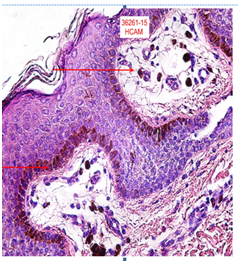

A skin biopsy was done and found hyperkeratosis skin, irregular hyperplasia of the epidermal rete ridges accompanied by mild and focal basal hyper pigmentation (Figure 5), papillary dermis presents a little lymphocyte infiltration and several small dilatedvessels accompanied by an increase of fat cells to the dermis. Focal rise of fatty tissue in the narrow (Figure 6). X-rays show decreased bone mineralization in the hands and feet and sclerotic joints in the feet. Her skull CTS, pelvic and thyroidal ultrasound were all normal. The patient has 46xx Blood cerotype, 17 hydroxy progesterone hormones, ACTH, normal AM cortisol. Thyroidal examination alteration, sub-clinic hypothyroidism, under pediatrics endocrinology treatment using levothyroxine.

Figure 5 Hyperkeratosis skin, irregular hyperplasia of the epidermal rate ridges accompanied by mild and focal basal hyper pigmentation.

Figure 6 Papillary dermis presents a little lymphocyte infiltration and several dilated small vessels accompanied by an increase of fat cells to the dermis.